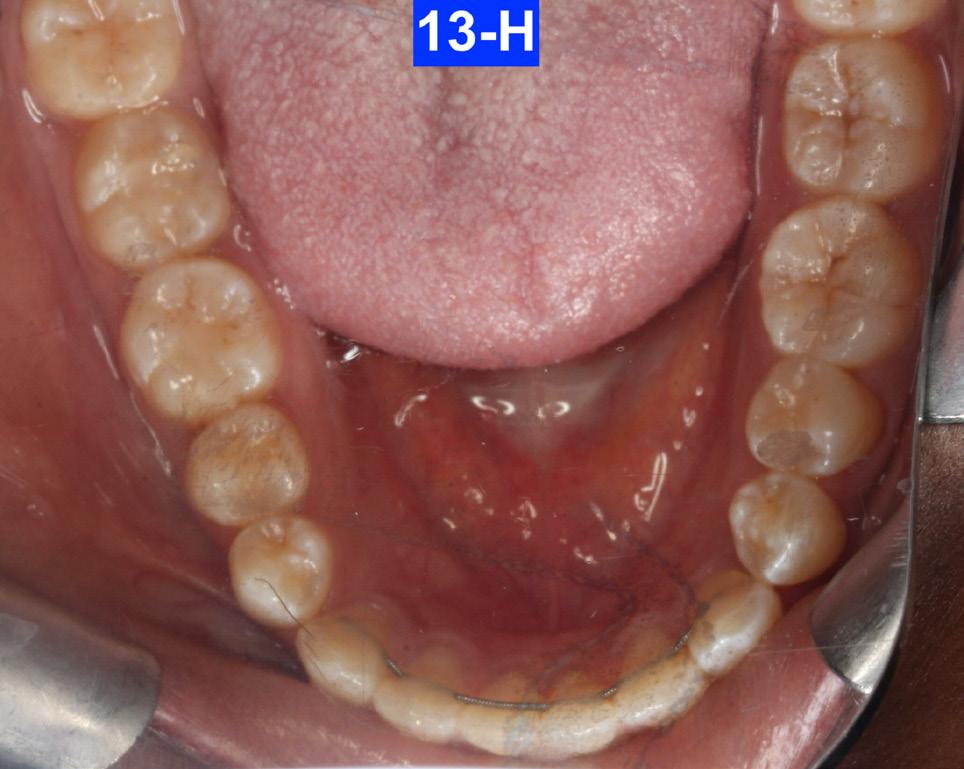

Fig. 13-H: 3 years post-treatment, MN occlusal view

The patient reported that she had not been wearing her retainer, no longer sucked her thumb, and no longer performed the OMT exercises (Figures 13A-O).